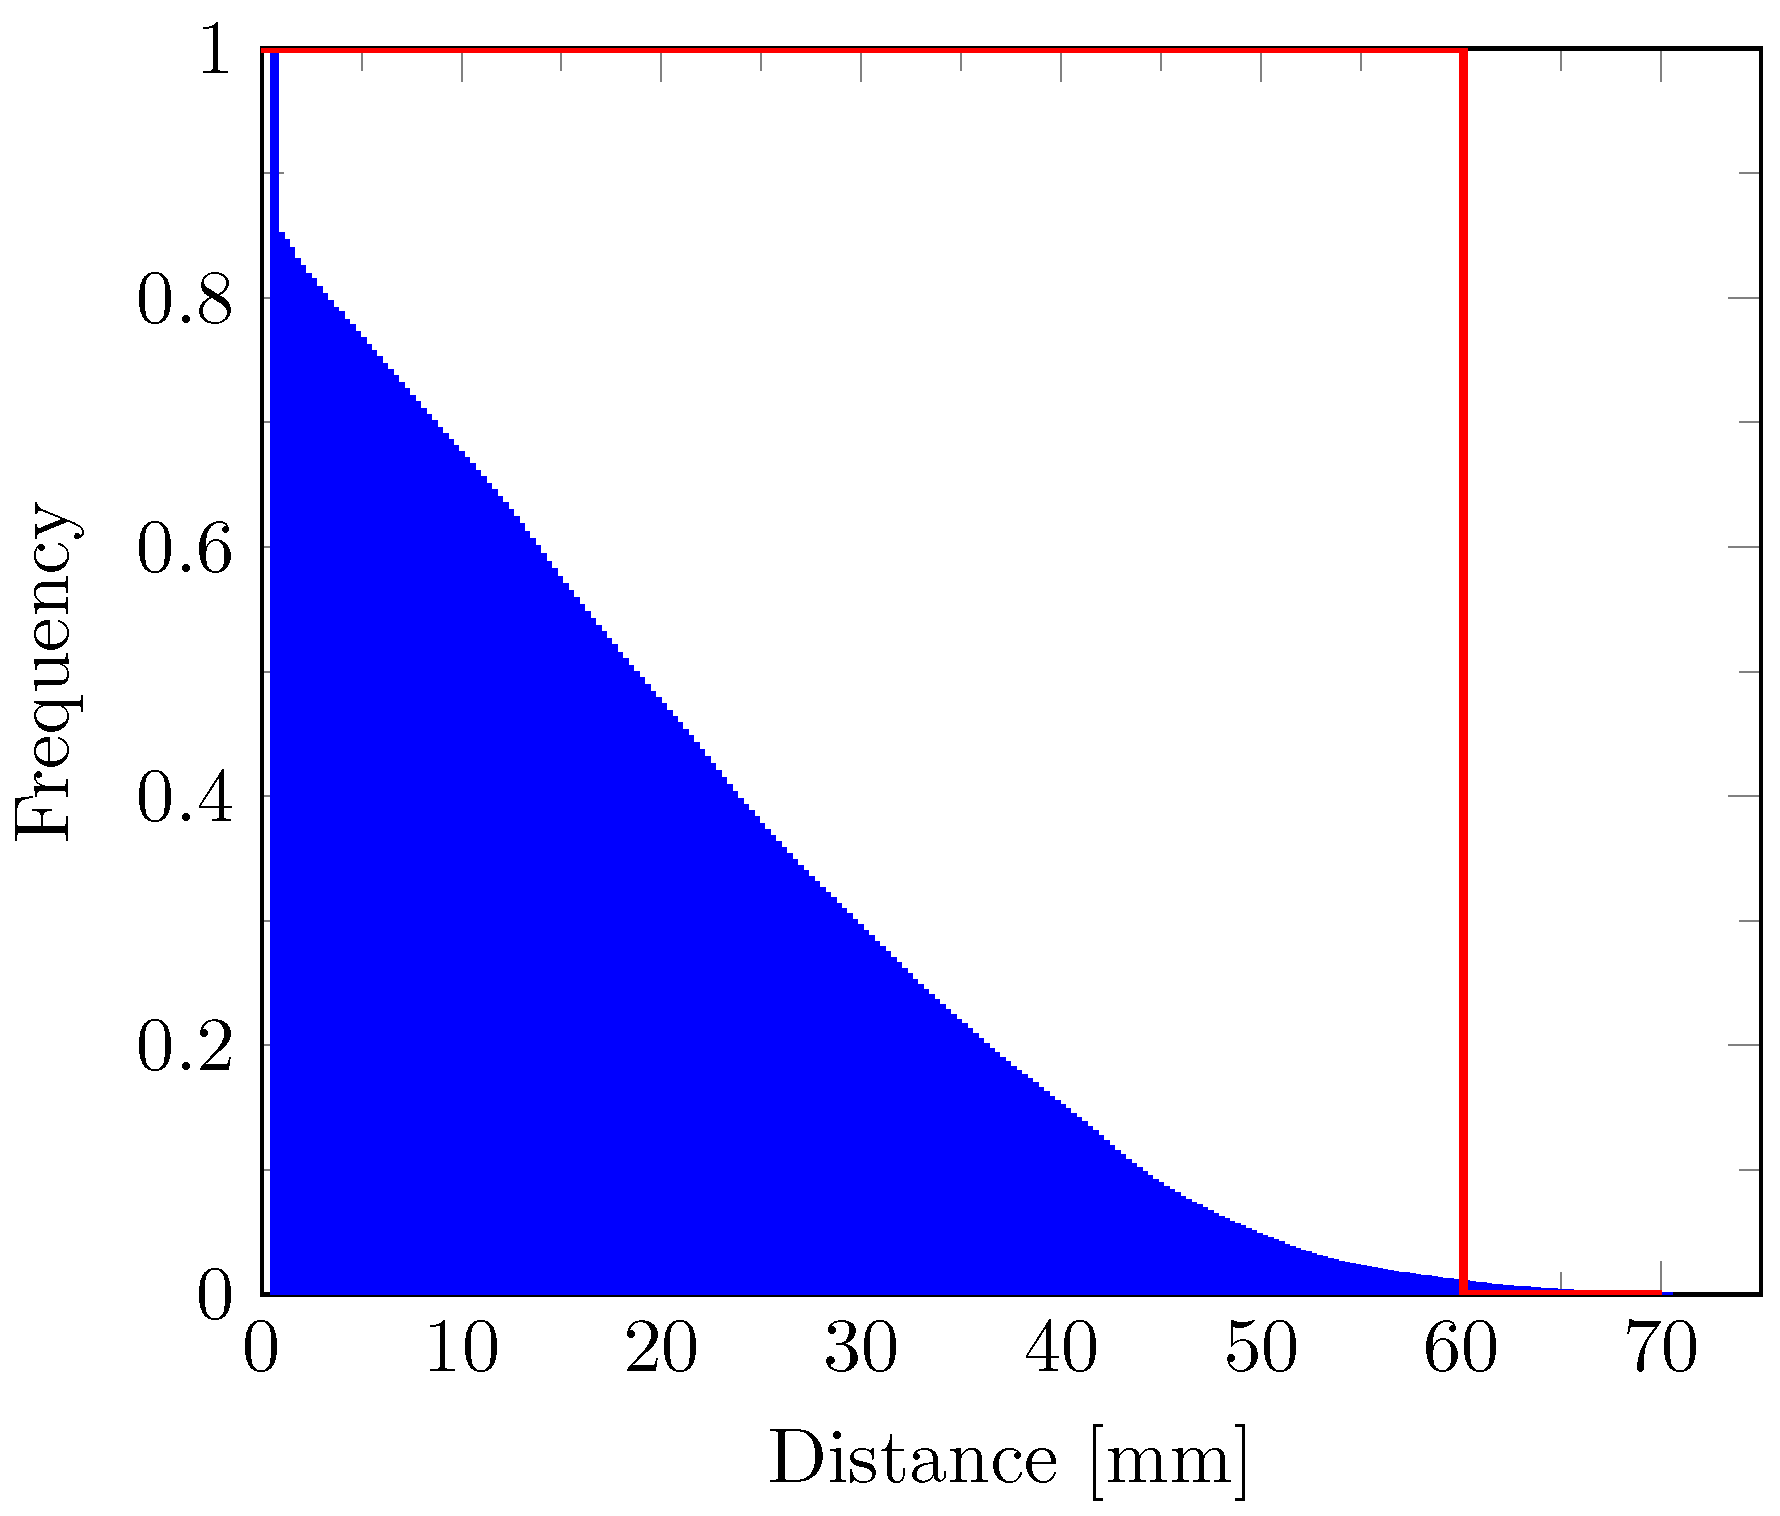

2.8. Distance Map

2.9. Cell Density Model

3. Results